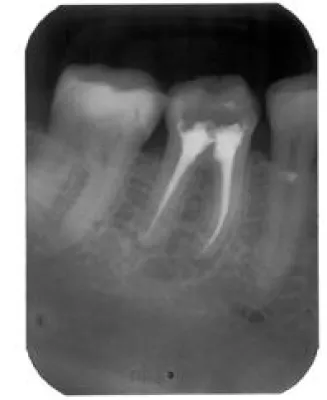

A und O der erfolgreichen Zahnwurzelbehandlung ist eine gründliche Reinigung der entzündeten Zahnwurzel mit ihren Nebenverästelungen und -kanälen! Ein speziell hierfür entwickeltes Operationsmikroskop macht die Wurzelkanäle und feinen Verästelungen gut sichtbar. Die Reinigung und Sterilisation der Wurzelkanäle erfolgt mechanisch, chemisch, per Ultraschall, Laser und mit Spüllösungen so lange, bis optimale Sauberkeit herrscht. Ist dieser Zustand erreicht, werden die ausgeräumten Wurzelkanäle mit möglichst zuvor auf Verträglichkeit getesteten Materialien gefüllt und verschlossen. Diese Methode ist sehr aufwendig und erfordert von ärztlicher Seite erstklassige technische Ausstattung sowie Kenntnisse in der ganzheitlichen Zahnmedizin.